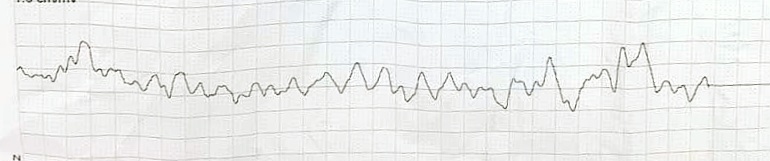

Initial electrocardiogram demonstrated diffuse ST-segment depression with ST-elevation in leads aVR and V1. The patient subsequently developed ventricular fibrillation requiring immediate cardiopulmonary resuscitation and defibrillation. During emergency transfer to the cardiac catheterization laboratory, she experienced recurrent ventricular fibrillation and profound cardiogenic shock.